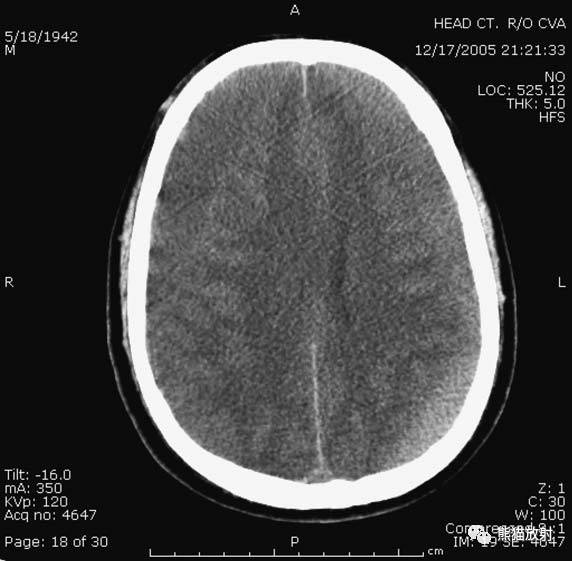

左侧大脑中动脉供血区脑梗死(亚急性期):低密度,轻度水肿。

缺血性脑卒中发作2-4天时,占位效应最明显。